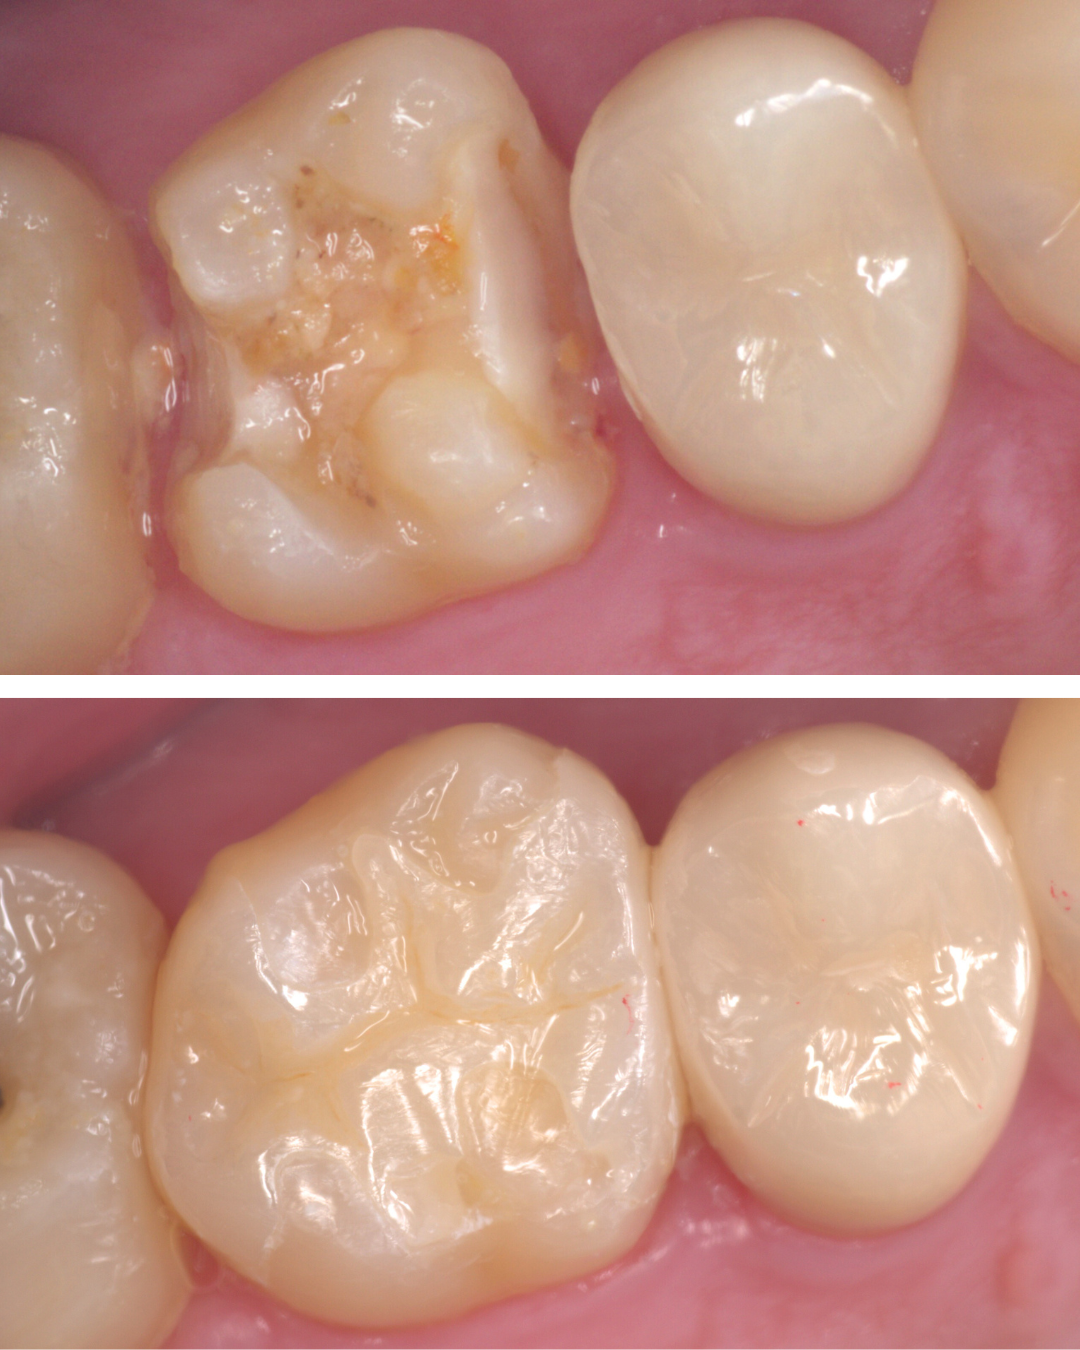

虫歯を取り残さないための「う蝕検知液」

虫歯を取り残してしまう原因は何でしょうか?

それは虫歯が一目見ただけではわからないからです。

黒くても削らなくていい場合もあります。黒くなくても削らなければいけない場合もあります。

う蝕検知液とは、虫歯の部分のみを赤く染める薬剤です。

写真は、虫歯治療をしている途中の写真です。どこに虫歯があるかわかりますか?

赤く染まった部分が虫歯です。

そして、虫歯を取り切った写真を見るとかなり大きな虫歯であった事がわかります。

虫歯治療を行う上で一番大切な事は、虫歯に感染した部分をしっかり除去することですが、まずは虫歯の硬さを頼りに、軟らかくなった部分を削っていきます。

「虫歯の部分だけを削るドリル」を使用すれば、それだけでほぼ虫歯は取り除けますが、感染部位を完全に除去できたかわかりづらい時もあります。

このう蝕検知液を併用することで、虫歯を取り残すことなく虫歯治療ができます。

う蝕検知液で細かくチェックする事で、虫歯治療の精度があがります。